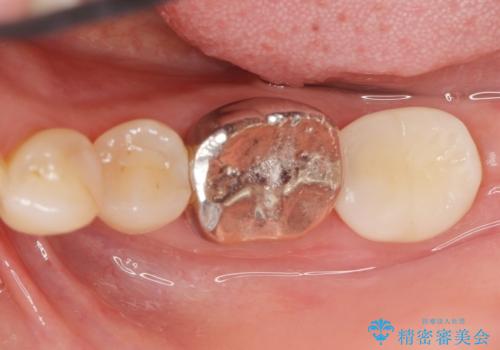

移植後、生着を待って根管治療及び補綴修復を行いました。

親知らずの移植により、自分の歯を用いて咬合機能を回復することができ、大変喜んで頂けました。

被せ物の種類:オールセラミッククラウン スタンダード